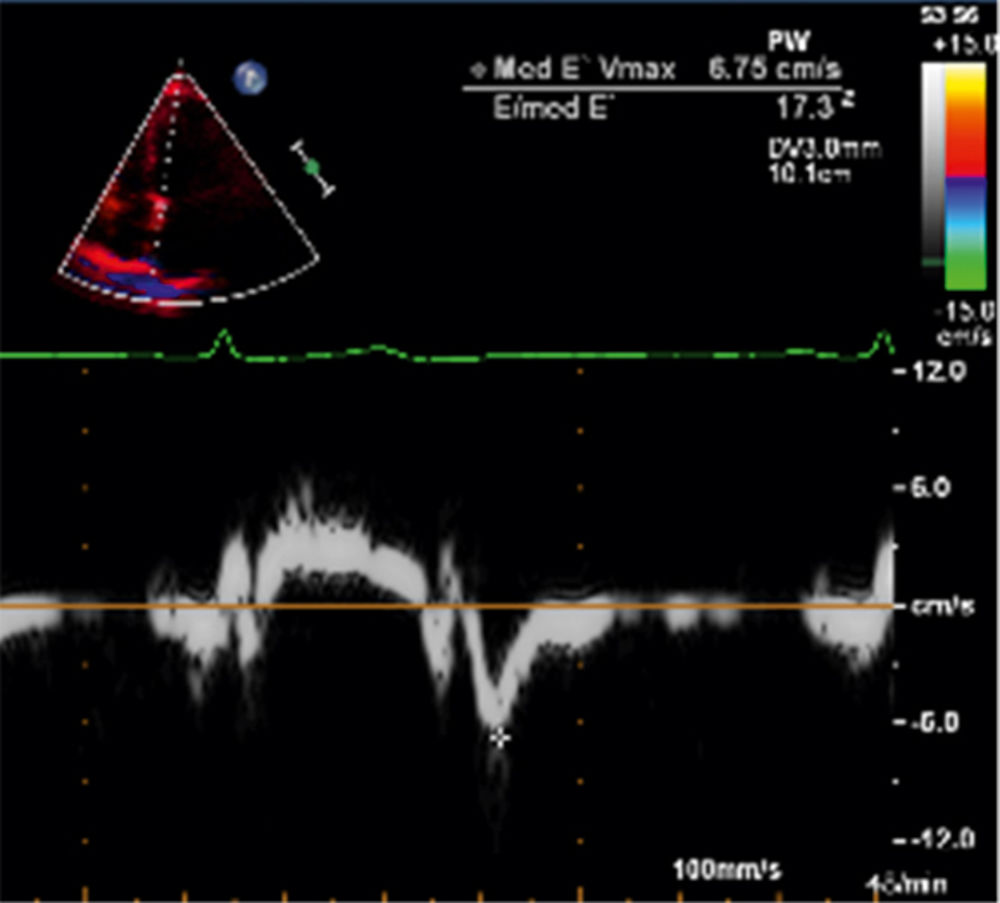

Echokardiografisch zeigte sich eine systolisch normwertige Ejektionsfraktion (EF) mit 60 Prozent und kein Anhalt für Wandbewegungsstörungen, jedoch Nachweis einer linksventrikulären Hypertrophie von zwölf Millimetern und Dilatation des linken Vorhofs. Mit einem inversen E/A-Verhältnis und E/E` (Echokardiografie-Parameter zur Bestimmung der Steifigkeit des linken Ventrikels) von 17,3 ergab sich die Diagnose einer diastolischen Dysfunktion (Abbildung 4).

Abbildung 4: Tissue Doppler Imaging; E/E`17,3.